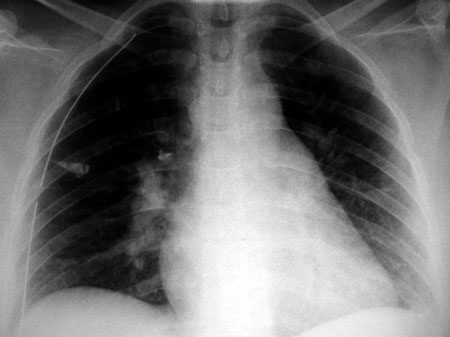

– ΗΚΓ: φλεβοκομβική ταχυκαρδία (ΚΣ = 127/λεπτό) και μη ειδικές αλλοιώσεις, όπως στροφή του άξονα κατά +1700, αρνητικά επάρματα «Τ» στην απαγωγή ΙΙΙ και σχετικά υψηλά επάρματα «R» στις II και V5 απαγωγές (εικόνα 1).

Εικόνα 1

Εικόνα 1. Ηλεκτροκαρδιογράφημα της ασθενούς κατά την αρχική εξέταση.